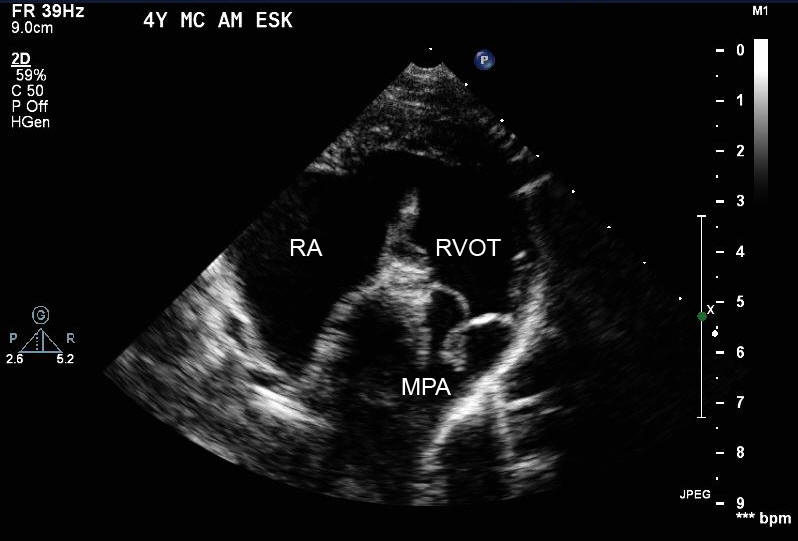

Canine blood donation and the effect on the heart using veterinary ultrasound